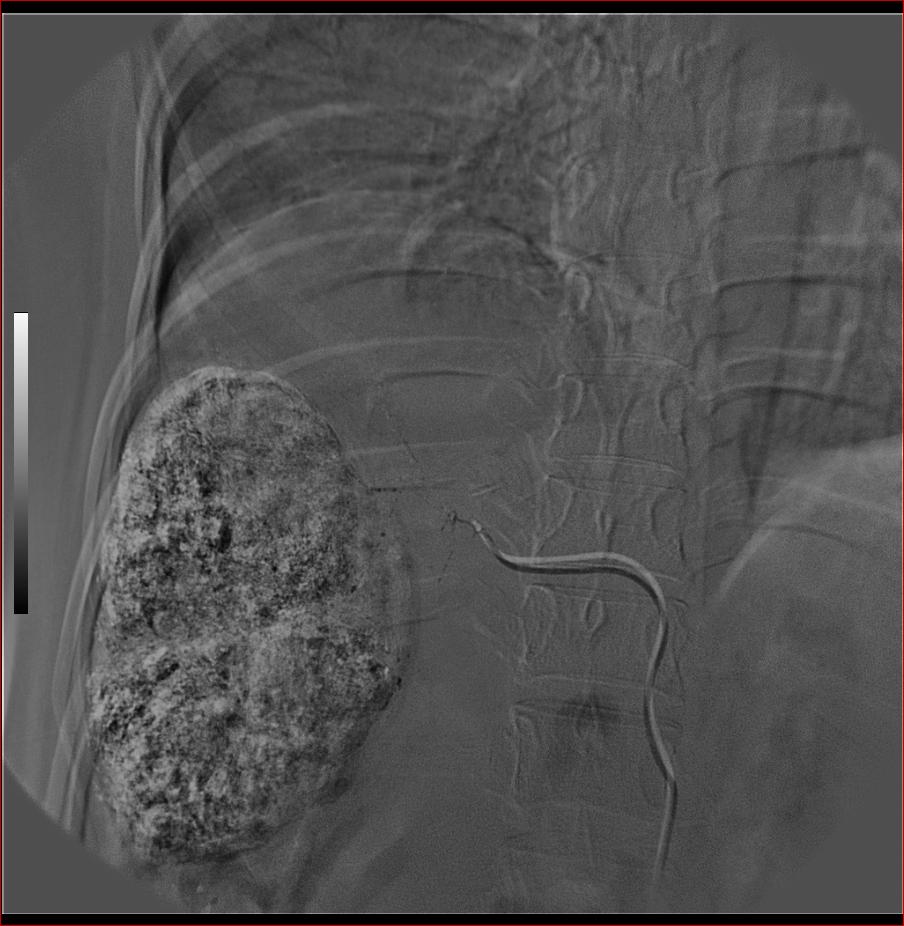

标题: DSA0138:F38Y,肝脏病变

第一次:

好牛的,右肝动脉发自肠系膜上动脉,不用微导管分次进行末梢栓塞,肿瘤染色完整。再次学习了。